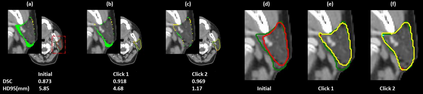

Automatic segmentation of anatomical structures is critical for many medical applications. However, the results are not always clinically acceptable and require tedious manual revision. Here, we present a novel concept called artificial intelligence assisted contour revision (AIACR) and demonstrate its feasibility. The proposed clinical workflow of AIACR is as follows given an initial contour that requires a clinicians revision, the clinician indicates where a large revision is needed, and a trained deep learning (DL) model takes this input to update the contour. This process repeats until a clinically acceptable contour is achieved. The DL model is designed to minimize the clinicians input at each iteration and to minimize the number of iterations needed to reach acceptance. In this proof-of-concept study, we demonstrated the concept on 2D axial images of three head-and-neck cancer datasets, with the clinicians input at each iteration being one mouse click on the desired location of the contour segment. The performance of the model is quantified with Dice Similarity Coefficient (DSC) and 95th percentile of Hausdorff Distance (HD95). The average DSC/HD95 (mm) of the auto-generated initial contours were 0.82/4.3, 0.73/5.6 and 0.67/11.4 for three datasets, which were improved to 0.91/2.1, 0.86/2.4 and 0.86/4.7 with three mouse clicks, respectively. Each DL-based contour update requires around 20 ms. We proposed a novel AIACR concept that uses DL models to assist clinicians in revising contours in an efficient and effective way, and we demonstrated its feasibility by using 2D axial CT images from three head-and-neck cancer datasets.